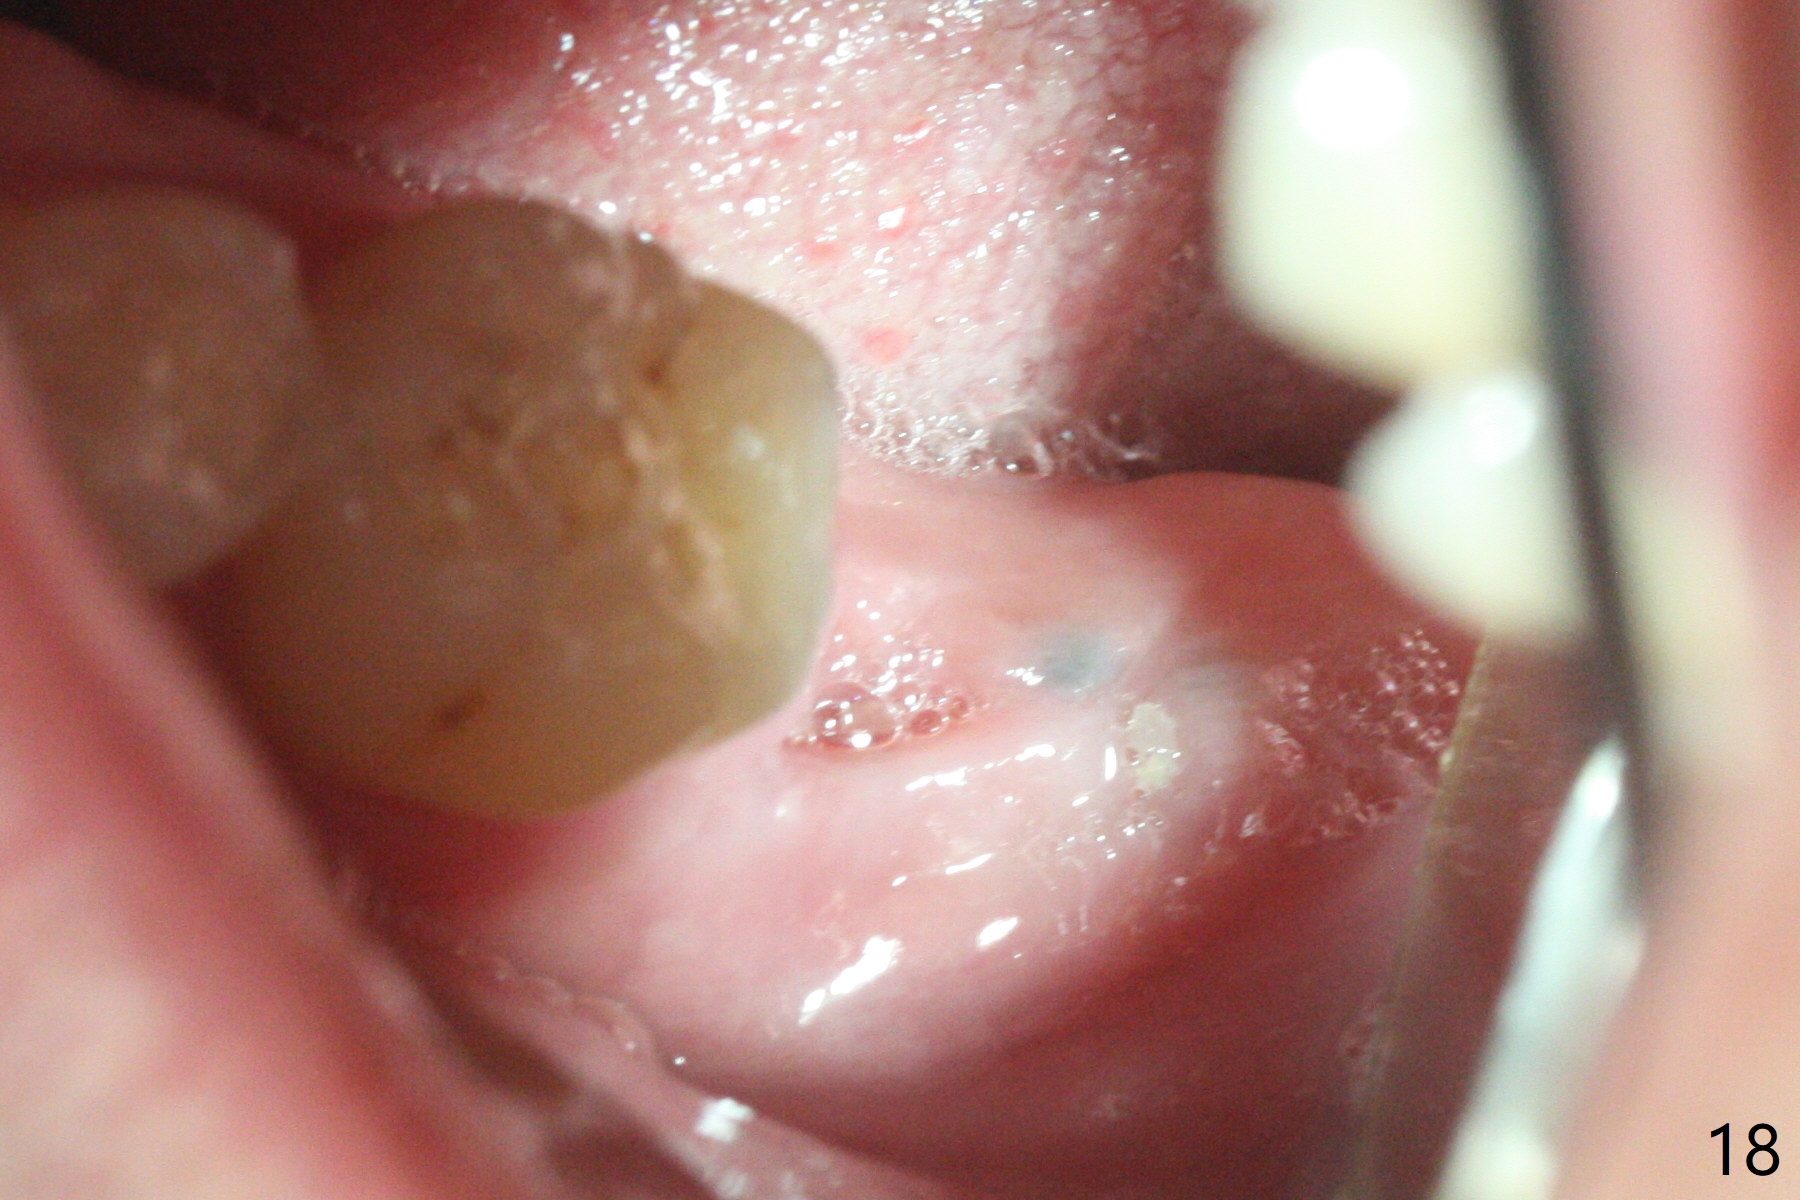

After placement of a 5x11 mm implant and cover screw at #18, allograft mixed with PRF (sticky bone) is placed in the peri-implant space, but it appears that bone density in the apical region (Fig.1 A) is lower than that in the coronal one (C) because of a constriction between the implant and the distal crest (*). Ideally the undercuts (Fig.2 *) of the extraction socket (black area) should be identified. Place bone graft in the undercuts (Fig.3 red circles) after osteotomy (white outlines) and before implant placement! A 4.5x1 mm temporary abutment is placed for an immediate provisional. The 2nd shortcoming of this case is that the implant is placed a little buccal. The papilla mesial to the immediate provisional (Fig.4 P) looks normal 4 days postop (no food impaction is expected when a final restoration is cemented). Additional acrylic (*) was placed to close a buccal gap when the provisional was seated with the temporary abutment. The patient reports loss of a piece of material in 4 days. It must be the additional acrylic, since it is absent 6 weeks postop (Fig.5). The provisional (Fig.5 P) looks wide, probably related to post-extraction gingiva and bone atrophy (Fig.6, 7 *). Bone graft (Fig.6 <) becomes a component of the gingival cuff. The provisional is re-trimmed for better oral hygiene. The gingival cuff is basically healthy 3.5 months postop, although the temporary abutment is loose and the implant is tender to rewinding and winding (Fig.8). The implant seems to remain non-osteointegrated 3.5 months postop (Fig.9). Although the bone density around the implant increases nearly 6 months postop (Fig.10), the implant remains tender when a 5x4(4) mm pair abutment is tightened. The healing abutment is reused. The bone density around the implant increases 11 months postop (Fig.11). Uncover is done with 5.5 mm profile drill. One month post uncover (12 months postop), the implant remains unstable (Fig.12). Prepare sticky bone x1. Make incision for exploration, including retightening the implant after Titanium brush and H2O2 Q-tip rubbing. If needed, a larger and shorter UF implant is a replacement (Fig.13). The implant is removed, cleaned with Titanium brushes and H2O2 in vitro and repositioned 12 months postop (Fig.14: arrow (gaps: post granulation tissue removal)). The gaps are regrafted with sticky bone and covered with PRF membrane and Cytoplast. Although the patient complains of severe pain the first 2-3 postop, the wound is apparently healing 12 days postop. The Cytoplast is exposed asymptomatic 5 weeks postop (Fig.16) and removed (Fig.17). The wound appears to have healed without loss of the bone graft (Fig.18).术后四个月伤口愈合,骨粉几乎没有丢失,有骨小梁形态(图十九:*)。切开,刮匙去骨,有一定硬度,即刻放置修复基台,完全就位(图二十),制备临时牙冠,牙周敷料固定组织瓣(没有缝线)。